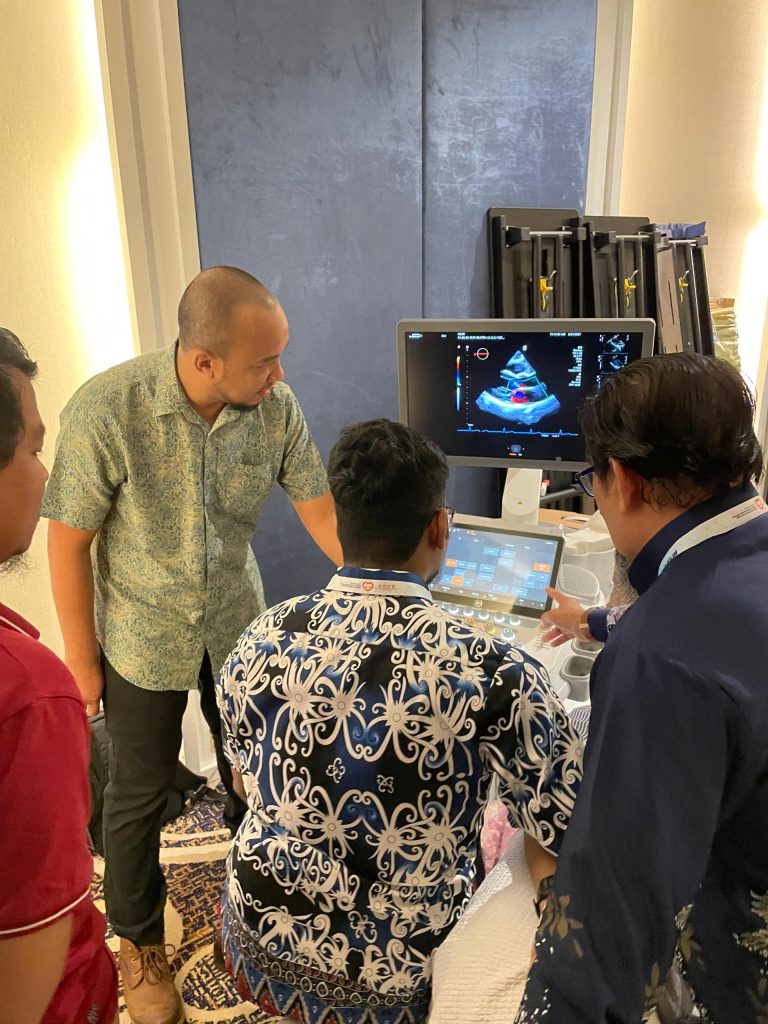

Innovative Diagnostic Devices

Partnering with Siemens Healthineers, we’re committed to patient care through cutting-edge imaging technology. Our offerings include an echocardiography system and general ultrasound for detailed organ and cardiac assessments. We also provide angiograms for comprehensive vascular insights, alongside our precise and versatile C-arm (mobile X-ray) for broader imaging needs. This integrated suite of tools empowers healthcare professionals with the detailed information vital for diagnosing, monitoring, and managing cardiovascular and other organ conditions, leading to improved patient outcomes and proactive health strategies

Clinical Application Support

Advanced medical imaging, a vital diagnostic tool that visualizes internal organs and structures with precision. Our state-of-the-art technology empowers healthcare practitioners with essential insights, facilitating accurate disease diagnosis and effective treatment planning. Additionally, our Clinical Apps Specialist provides continuous support to ensure seamless utilization of our cutting-edge imaging system.